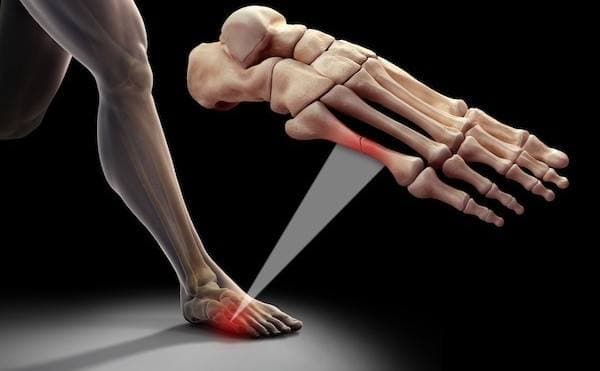

Stres Kırığı Tedavisi

Stres kırığı, aslında tam olarak bir kırık değildir. Ayağın yük taşıması sırasında her bölgenin farklı işlevleri...